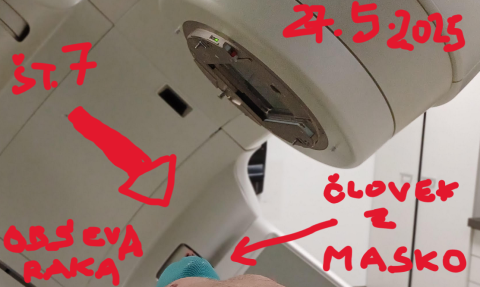

DIAGNOZA:RAK/30/ Ljubezen na prvi pogled: randi s številko 7...

Naslednje mesece bom v "dobri družbi"....

DIAGNOZA RAK/34/ Masko nosim kake pol ure - pa ni pustna...

Raka "cvrejo" in ga bodo še dolgo....

29. maj 2025